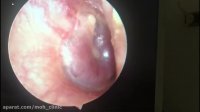

ترمیم پارگی پرده گوش

کلینیک MOH تیم جراحی سر و گردن

7.3 هزار نمایش

6 سال پیش